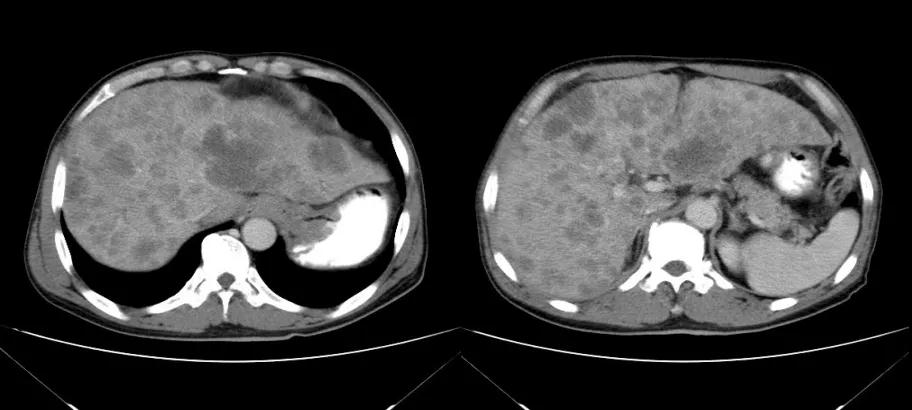

诊治经过:2020年11月25日患者行经皮动脉化疗灌注栓塞术(铂类+氟尿嘧啶);2020年11月30日免疫组化及基因检测结果为:ERBB-2扩增(9倍),VEGFR未突变,MSI微卫星低度不稳定,错配修复蛋白部分缺失(dMMR),MSH2(+弱),MLH1(-),MSH6(+),PMS2(-),CDX2(-),Villin(+),CK8/18(+),Ki67(5%+),CD56(-),Syn(-),CgA(-);患者为HER2阳性,患者肝脏病灶很多,残余正常肝脏体积小,需要寻找对肝功能影响小且抗瘤效果明显的治疗,因此联合吡咯替尼进行系统治疗。2020年12月14日复查结果提示肝脏病灶明显缩小(PR)。结果见图2。

图2